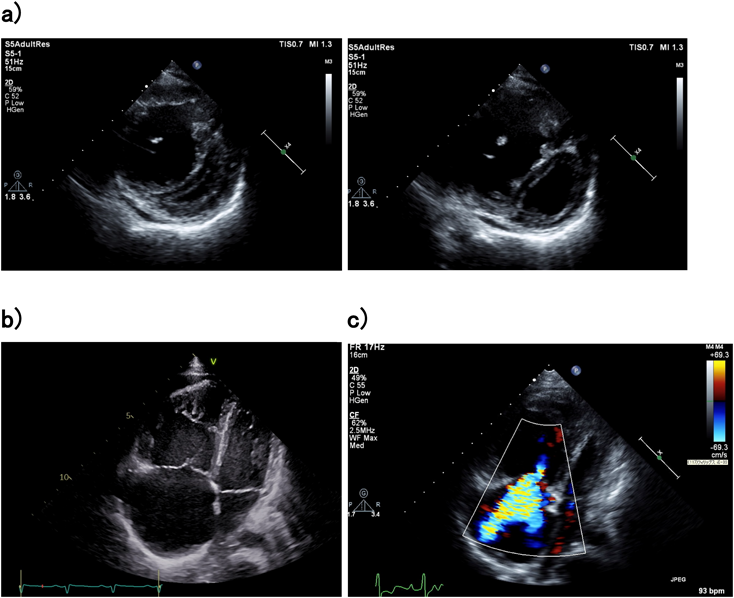

肺動脈性肺高血圧患者では,より進行した状態に至るまでは臨床症状に欠けるが,心エコーでは右室機能低下の所見が確認されることがある.右室肺動脈カップリングが維持されている場合,肺動脈圧が高い場合であっても右室内腔の拡大は極軽度であり下大静脈の呼吸性変動も認められ,三尖弁輪径は概ね正常である.進行すると徐々に右室肥大による代償性変化で対応することができなくなり,その結果maladaptive remodelingによって右室の内腔は拡大しeccentric hypertrophyを示す.この右心室の拡大によって三尖弁輪も拡大し三尖弁逆流を認めるようになり,さらに右室内腔の拡大が助長されて右室肺動脈アンカップリングの状態になる(Fig. 2a, b, c).また拡張期においても心嚢液貯留が認められる場合には,アンカップリングを示唆する重要な所見の1つである.肺動脈収縮期圧を評価する際に用いられる三尖弁逆流圧較差において,Doppler波形の描出が不十分である場合には過小評価になることが多いことや,右心機能が低下している症例では弁逆流が過小評価されることがあることに留意すべきである.

Fig. 2 Echocardiographic findings in patients with severe PAH

a) Parasternal short-axis view of the right ventricle and the left ventricle in children with severe pulmonary arterial hypertension. The left ventricle appears enlargement of right ventricle cavity and the interventricular septum curves into the left ventricle. b) Enlargement of right atrium and ventricle in severe pulmonary arterial hypertension from a 4-chamber view. c) A 4-chamber view shows severe tricuspid regurgitation with dilatation of right atrium.